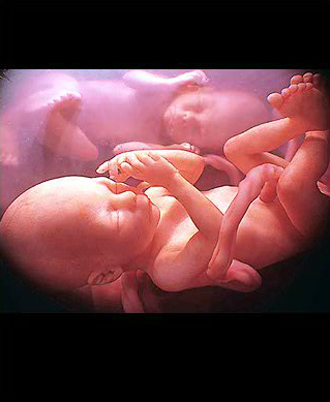

- 4차원 후기 정밀 초음파 (26~28주)